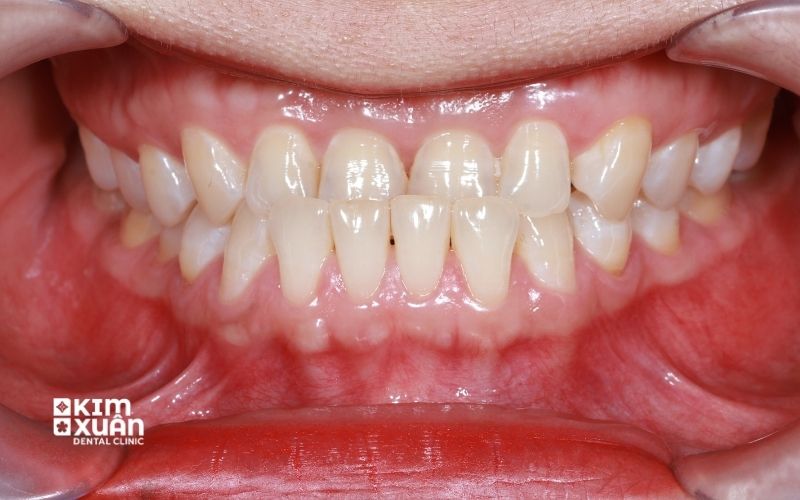

Niềng răng móm là phương pháp chỉnh nha giúp điều chỉnh khớp cắn ngược, trong đó răng hoặc hàm dưới đưa ra trước so với hàm trên. Tình trạng răng móm không chỉ ảnh hưởng đến thẩm mỹ khuôn mặt mà còn gây khó khăn khi ăn nhai. Nếu không điều trị sớm, răng móm có thể dẫn đến mòn răng, sai lệch khớp cắn và rối loạn khớp thái dương hàm về lâu dài.

Khi cắn lại, răng cửa hàm dưới che phủ hoặc chạm trực tiếp vào răng cửa hàm trên

Môi dưới và cằm nhô ra, khuôn mặt nhìn nghiêng có cảm giác lõm

Khớp cắn lệch, ăn nhai không thoải mái, dễ mỏi hàm